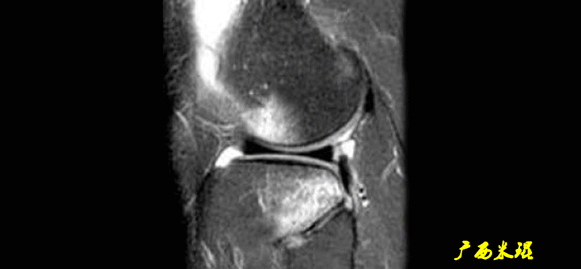

4)消失:

-

髁间窝空虚,无韧带信号。

见于较久的损伤,损伤的ACL撕裂较重呈马尾状,无滑膜包裹,逐渐被关节内的酶腐蚀而消失。